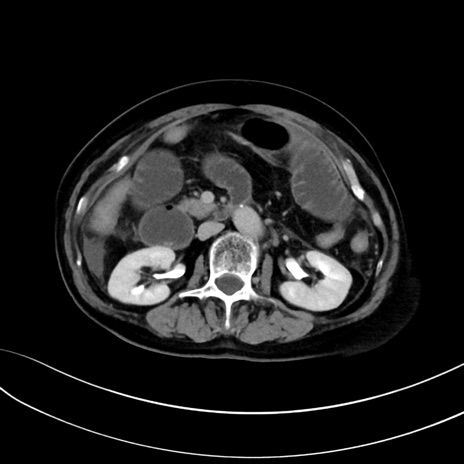

症例13 CT(横断像)1日半後